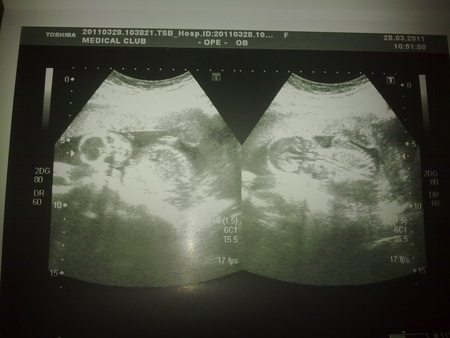

я вот и сама запуталась уже.....

один говорит одно,другой другое,вот и я в раздумьях......

Блин я тоже вижу писечку на последней фотке.......Блин у вас точно мальчик!!!!

у меня еще 8го будет УЗИ,и потом еще 21числа,если три раза скажут мальчик,то придется поверить!